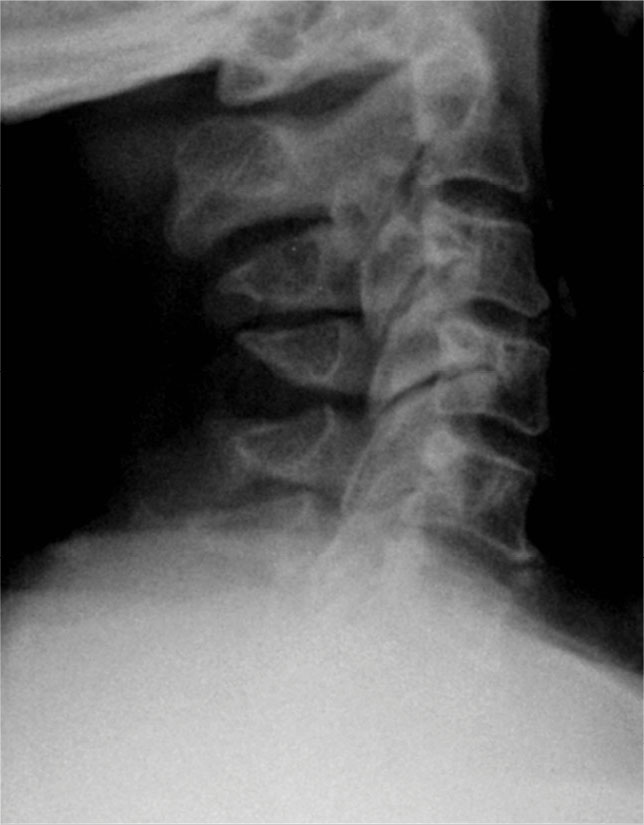

Pre-op dynamic radiographs demonstrate partial loss of disc height at C5-6 and C6-7 without instability or scoliosis.